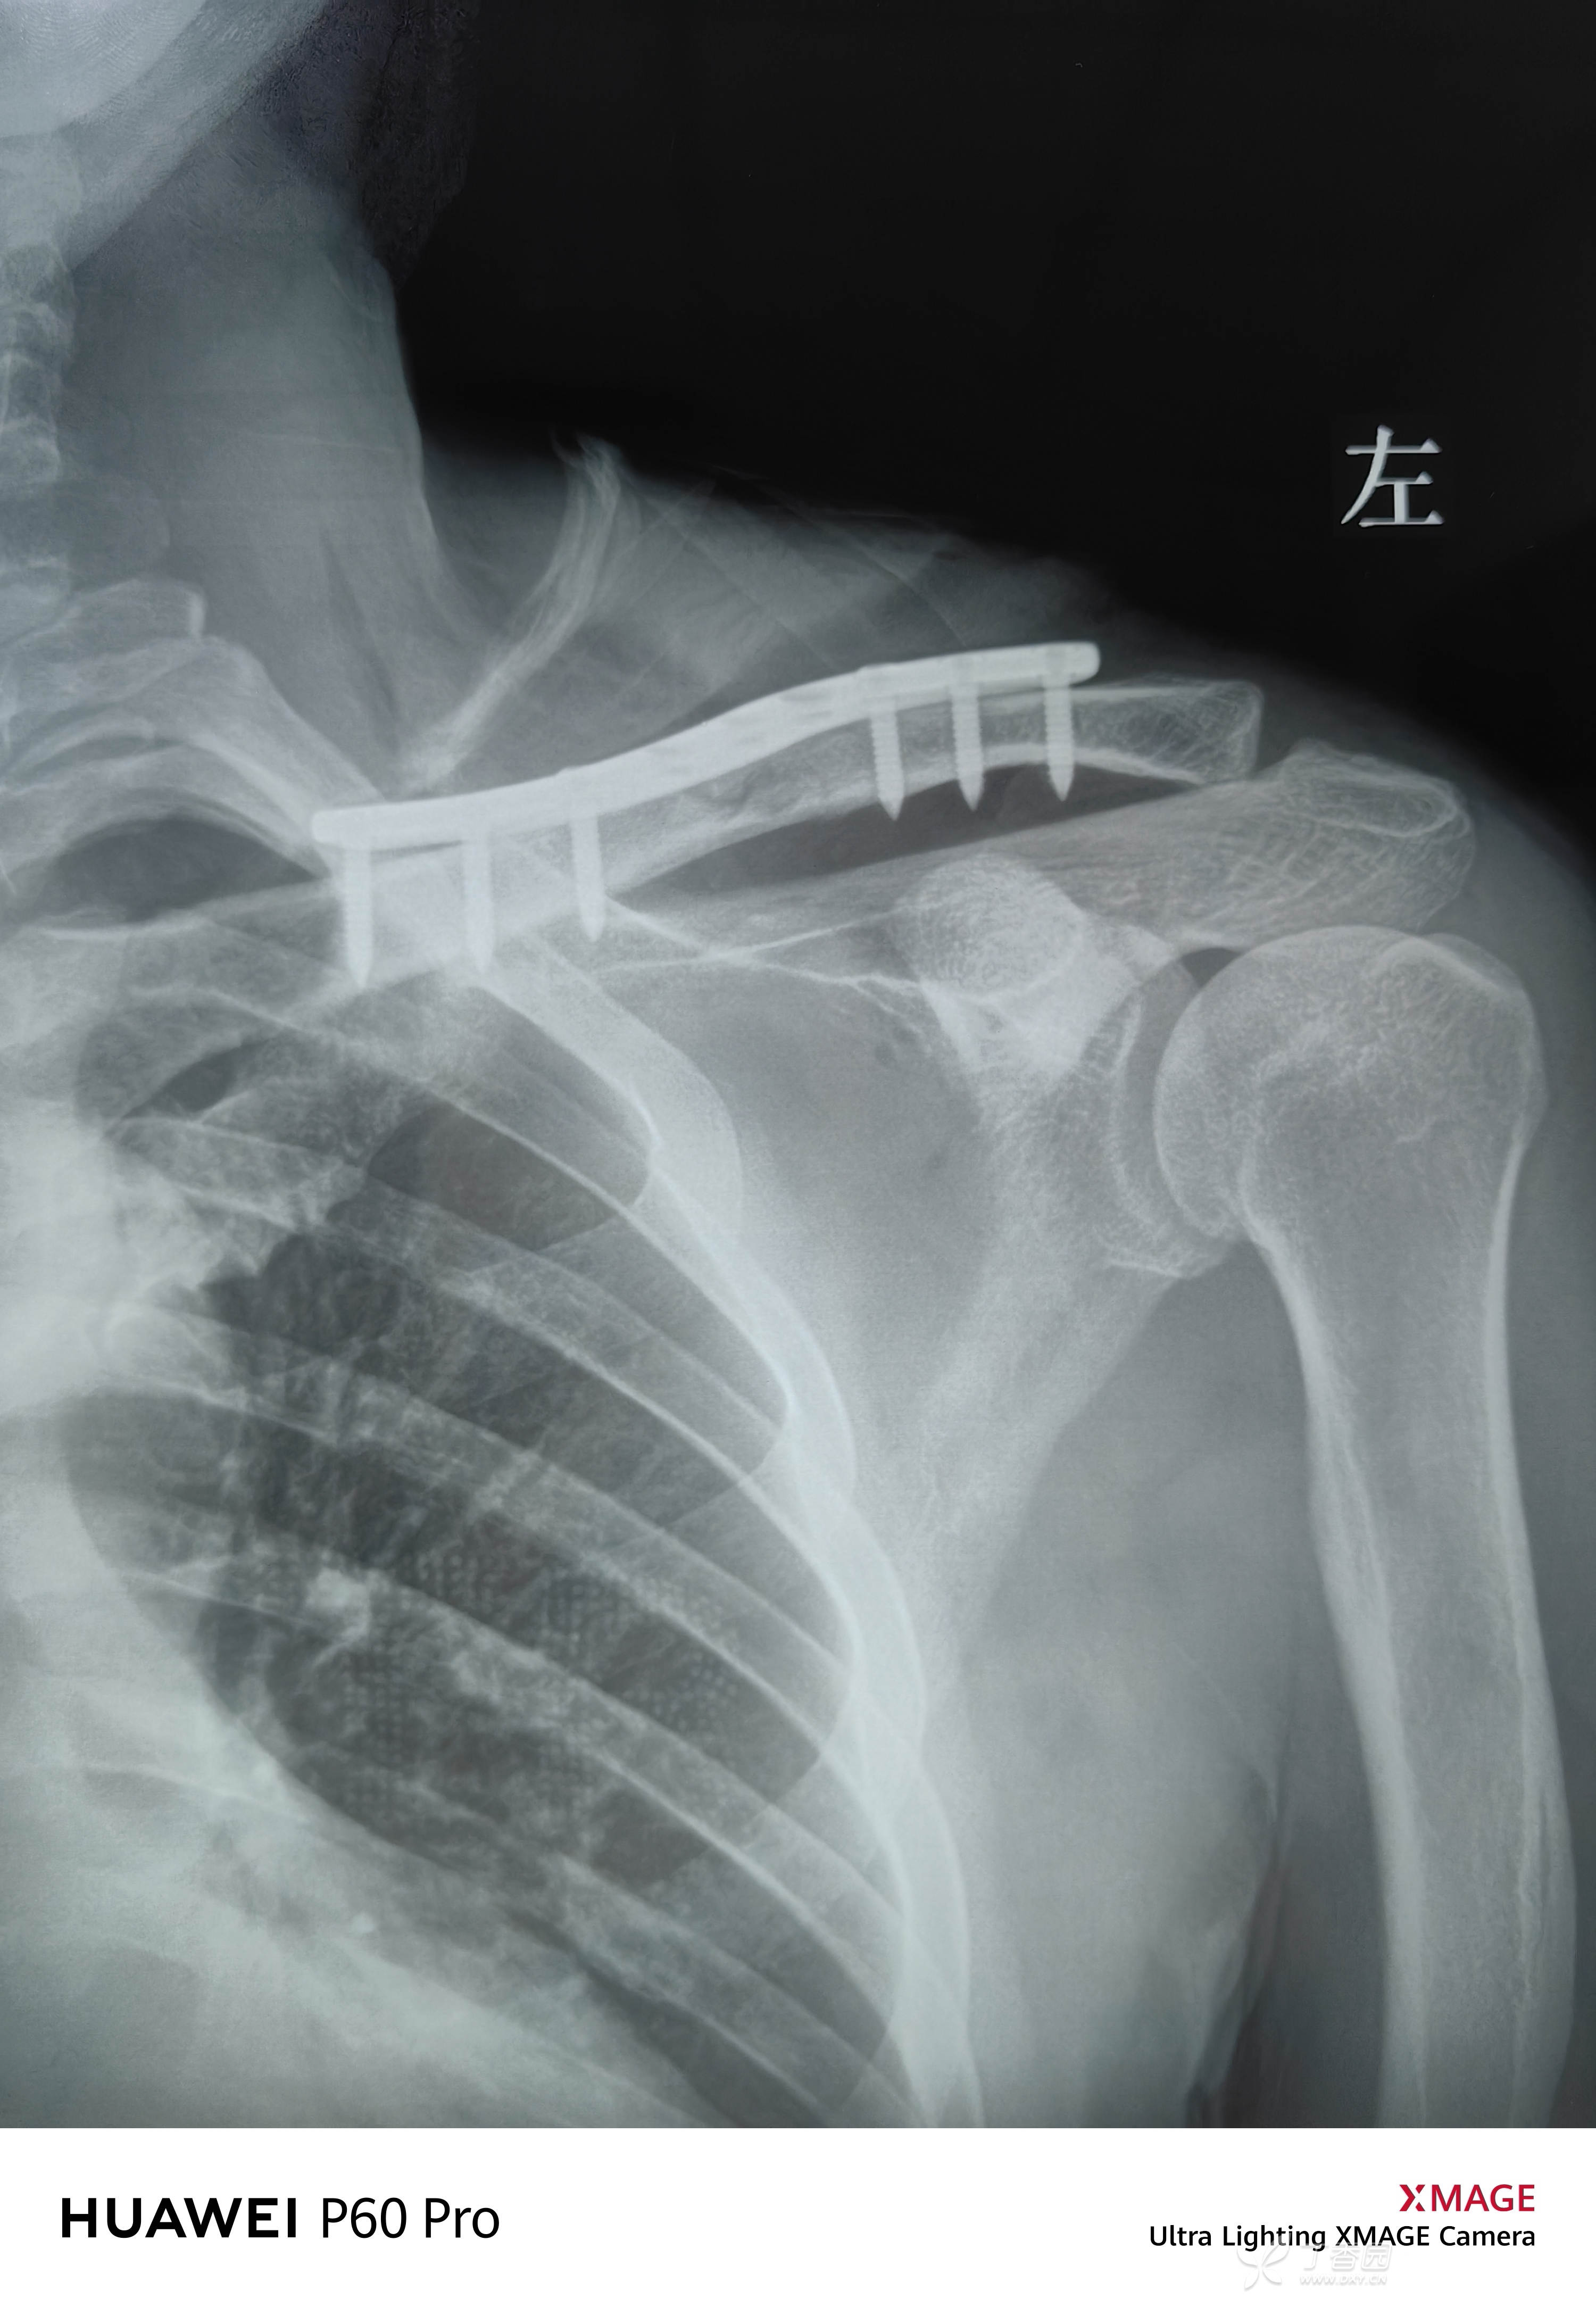

切开后可见锁骨粉碎性骨折,后侧,前侧各一大骨块,有骨膜相连

Nice结捆扎在钢板,女性,保护锁骨上皮神经

锁骨上皮神经,对女性患者乳房区域感觉尤为重要,建议常规保护

NICE结,捆扎骨块,临时固定后上钢板。

也可以捆扎在钢板上